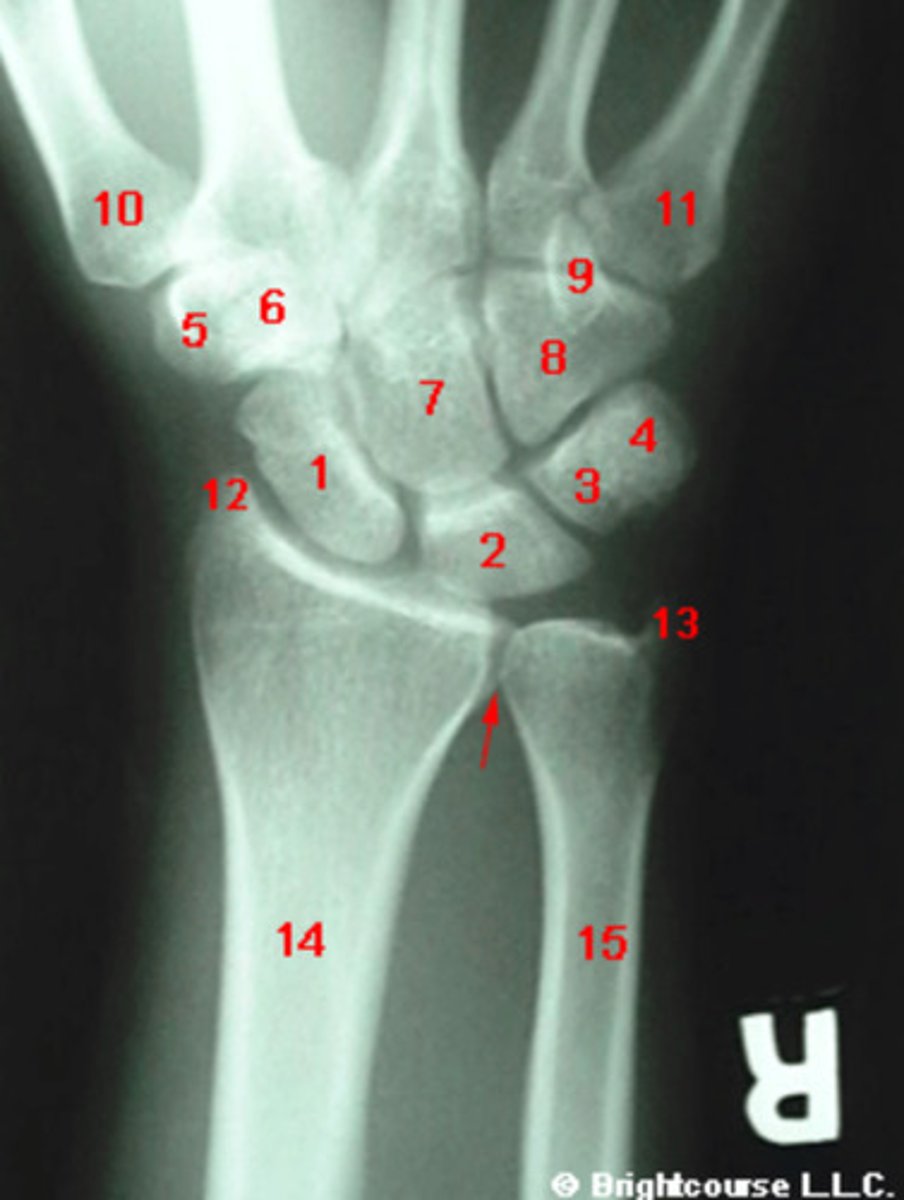

What structure is indicated by number 1?

What structure is indicated by number 2?

What structure is indicated by number 3?

What structure is indicated by number 4?

What structure is indicated by number 5?

What structure is indicated by number 6?

What structure is indicated by number 7?

What structure is indicated by number 8?

What structure is indicated by number 12?

What structure is indicated by number 13?

What structure is indicated by number 9?

What structure is indicated by number 10?